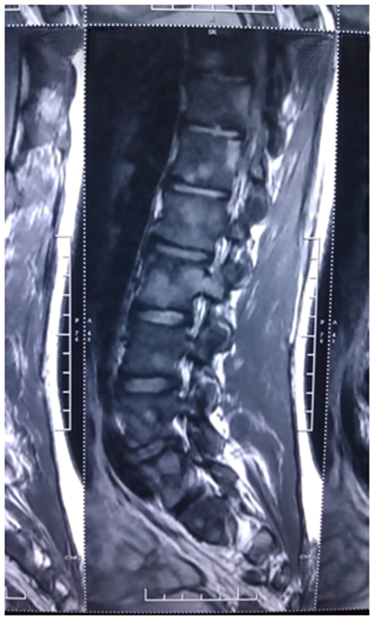

Patient’s complete blood count and peripheral smear was normal. The results of urine culture, blood culture and serology of viruses including EBV, CMV, hepatitis B, C and HIV were negative. Erythrocyte sedimentation rate: 68mm/h, C-reactive protein: 24mg/L (normal<5). HLAB27 was negative and mantaux was 14mm. Blood TB PCR, TB quantiferon Gold test and serology for Brucella was negative. X rays of the spine, pelvis and sacro-iliac joints were normal. Ophthalmological and skin examination was normal. MRI of the Sacro-iliac joint revealed diffuse patchy marrow edema in the bilateral sacro-iliac joints (Figure 1) involving bilateral sacral ala and juxta articular iliac bones and associated with diffuse patchy marrow edema in the vertebral bodies from thoracic to sacrum vertebrae. There was mild reduction of joint space in the bilateral sacro-iliac joint inferiorly with erosive changes in the articular surface of iliac aspect of right sacro-iliacjoint. MRI of whole spine revealed diffuse patchy marrow edema in the vertebral bodies (Figure 2). Bone marrow examination was essentially normal.

Figure 1 MRI of the Sacro-iliac joint revealed diffuse patchy marrow edema in the bilateral sacro-iliac joints.